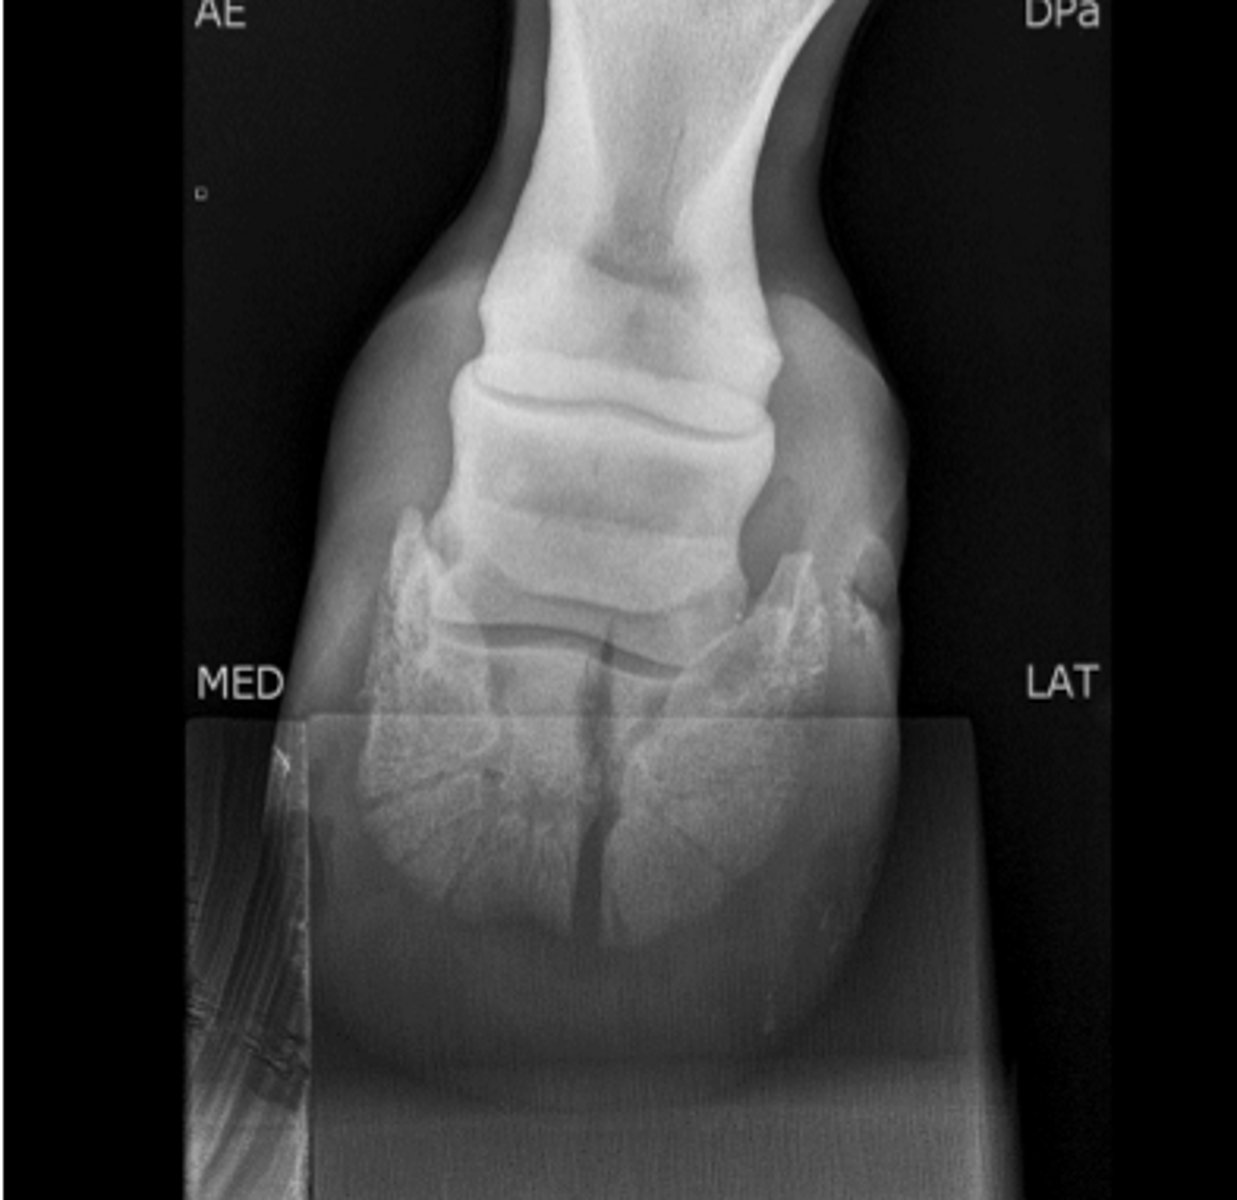

Long bone fracture

What is your top differential for this colt?

Tibia

Which bone is fractured?

Tarsus and stifle

Which joints require immobilization?

Robert jones bandage, lateral splint from the ground to the hip

What is the correct type of coaptation for this tibial fracture?

Internal fixation

How might you treat this fracture?